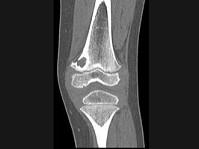

问题 男,12岁,大腿下部间歇性疼痛,劳累后加重,结合图像,最可能的诊断是?(?)

选项 A.纤维性骨皮质缺损 B.干骺端结核 C.骨样骨瘤 D.邻皮质软骨瘤 E.非骨化性纤维瘤

答案 A